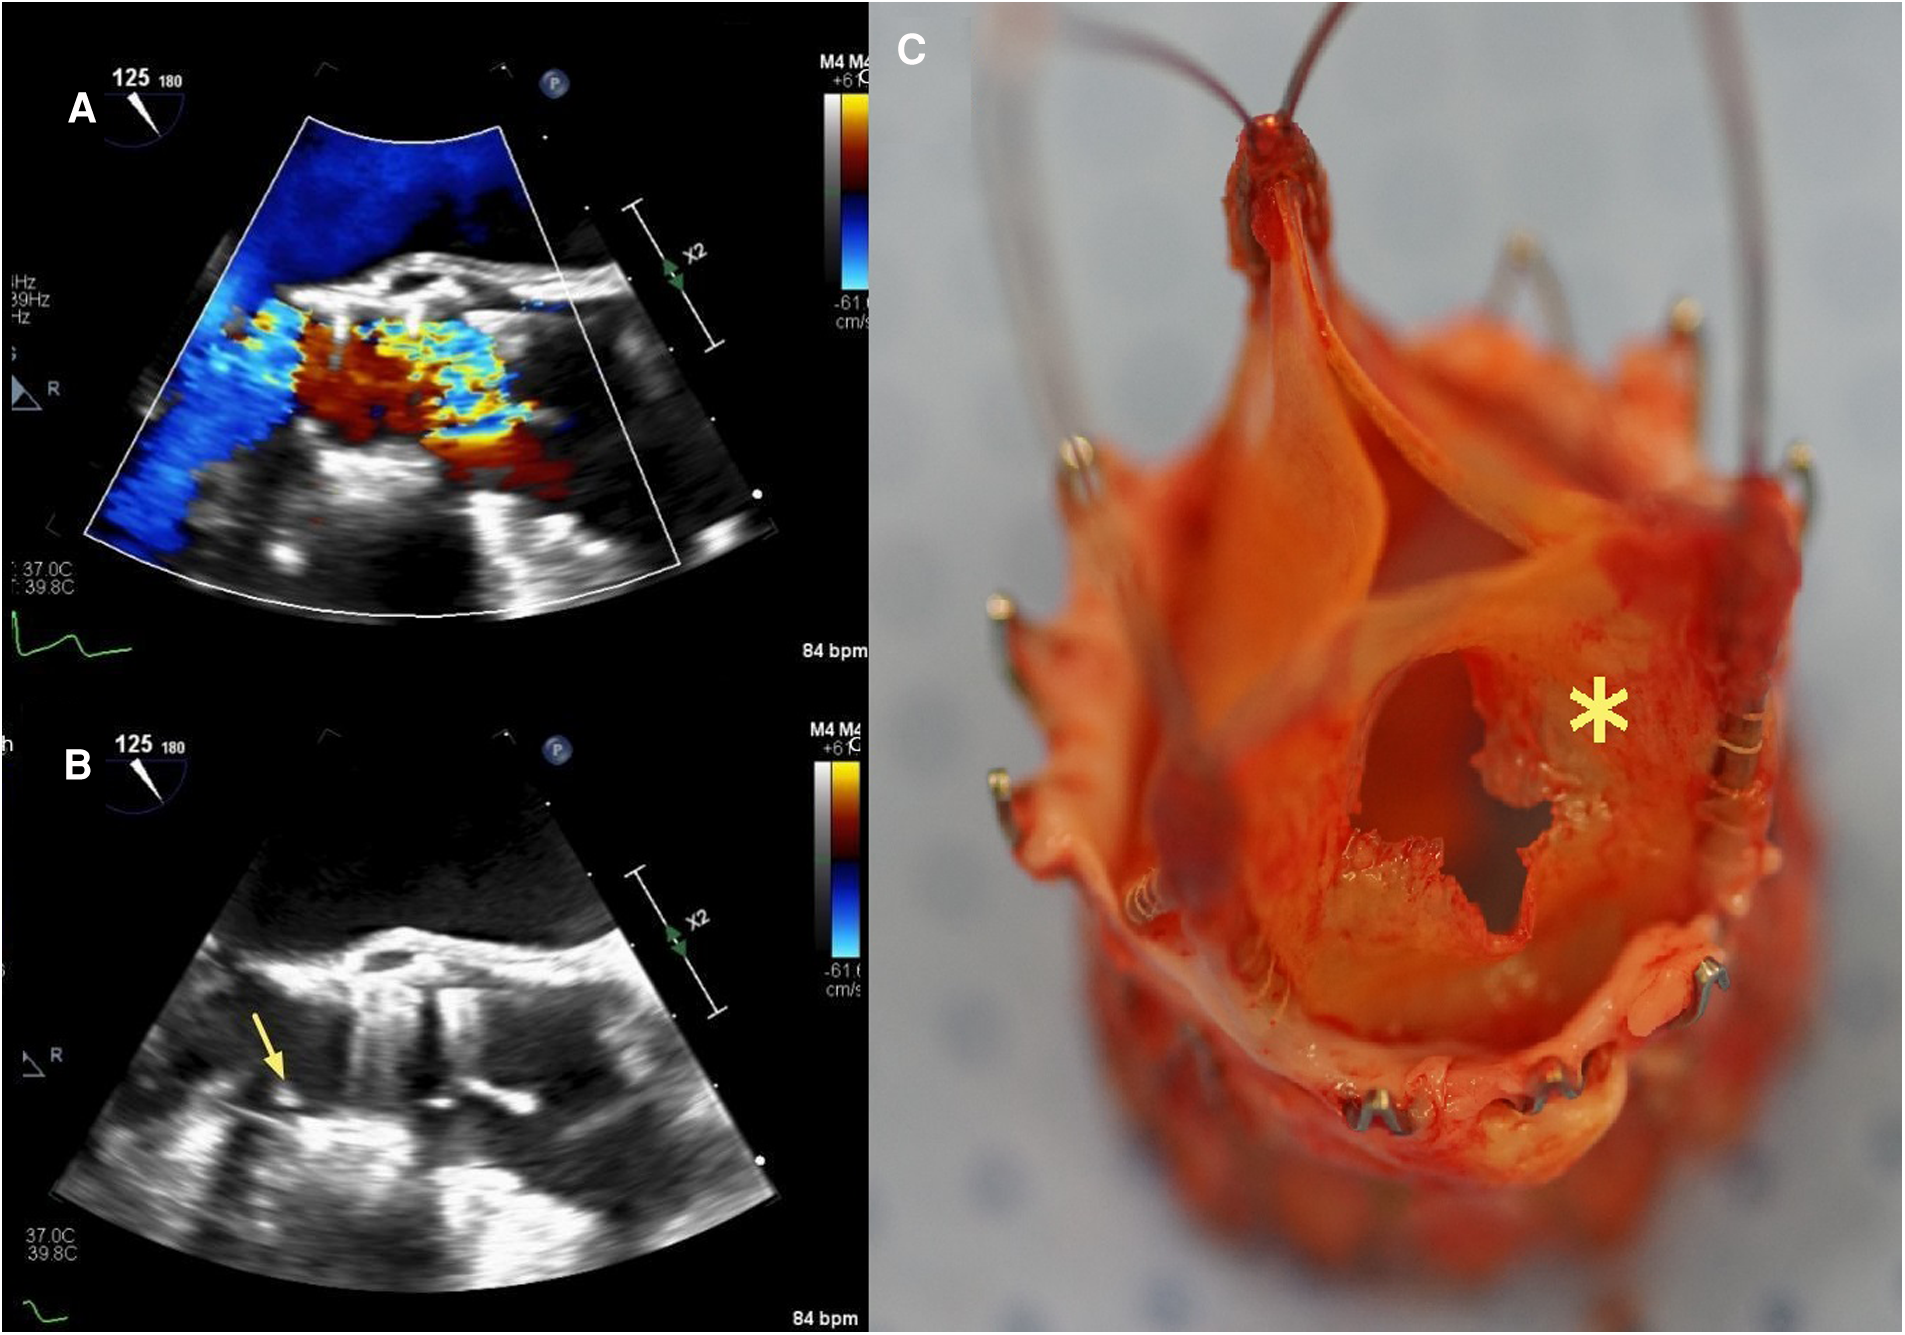

An 80-year-old woman was implanted with ACURATE Neo (size S) for symptomatic aortic valve stenosis. Moderate residual AR after valve deployment was immediately addressed with single balloon dilatation. TTE at discharge and at the 1-year routine control showed no significant regurgitation and low transaortic gradients. After barely 2 years (23 months), the patient complained of sudden dyspnea and medication-refractory elevated blood pressure. TTE performed by her cardiologist revealed a severe AR. TEE after admission at our center demonstrated a partial cusp prolapse on the right-coronary position associated with severe, eccentric AR (see Figures 2A,B). Blood cultures were negative. Given the intermediate surgical risk and to prevent coronary obstruction with limited coronary ostium height (13 mm on both sides), we opted for a TAVR explant and SAVR. Intraoperative inspection of the prosthesis revealed a central tear in the leaflet in the right-coronary position (see Figure 2C). There were no local signs of endocarditis. The extraction of the prosthesis was complicated due to an extensive pannus and endothelialization of the axial stabilization arches anchored in the aortic wall. After prosthesis removal, we implanted a 21-mm surgical bioprosthesis in the aortic position. The postoperative course was besides transitory acute-on-chronic renal failure uneventful, and the patient was discharged after 10 days. Cases summary as timeline is provided in Table 2.

Figure 2

Case 2: transesophageal echocardiography three-chamber view with color-flow Doppler (A) and aortic valve-centered short-axis view with color-flow Doppler (B) showing severe intraprosthetic regurgitation and partial cusp prolapse (yellow arrow) on the right coronary side, respectively. (C) Explanted ACURATE Neo prosthesis with a central tear in the leaflet in the right-coronary position (yellow asterisk).